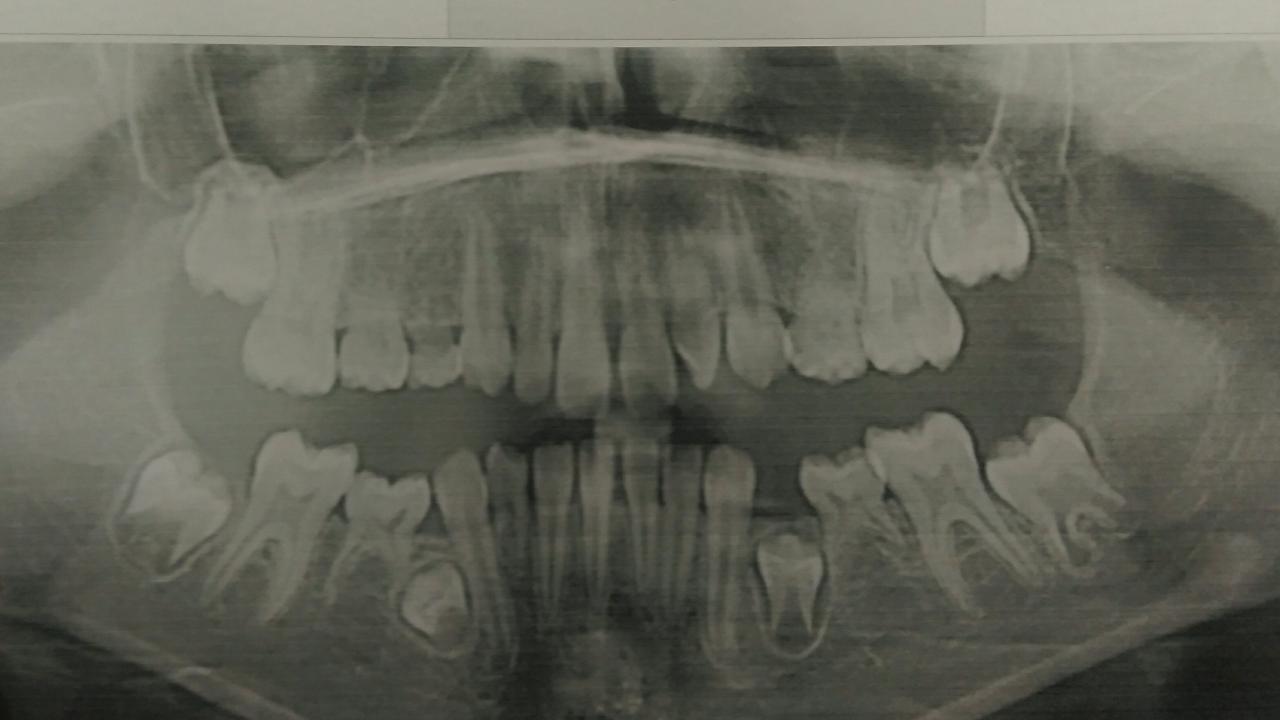

А у меня такое расстройство недели - тоже под импланты в далеком будующем....Нажмите на изображение для увеличения

Нижний молочный клык пора удалить.

Ага...и ортодонтам показаться, начать расчитывать место под импланты и планировать улыбку....

Я вообще ж не детский доктор, у меня под присмотром только пятеро детей друзей-кумовей без особых проблем, так, 1-2 пломбочки, зато из 5 детей у 4х адентия

Место под импланты есть. Его надо будет удержать. Когда верхние молочные начнут уходить. До этого не мешало бы провести коррекцию положения имеющихся постоянных зубов.